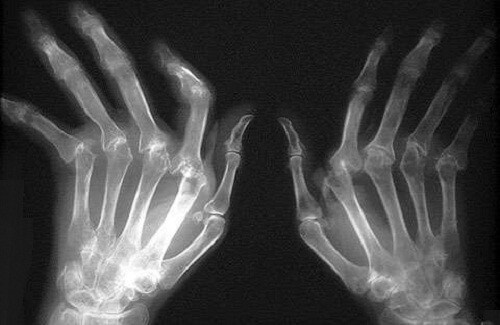

Quando se vive com artrite reumatóide (AR), a escovagem, fio dentário, e visitas regulares ao higienista/dentista são especialmente importantes. Estudos mostram uma forte ligação entre AR e doença periodontal, uma condição inflamatória que pode levar à perda de dentes e outras complicações de saúde, como doença cardíaca.

Um estudo alemão publicado em junho de 2008 no Journal of Periodontology mostrou que as pessoas com AR tinham oito vezes mais probabilidades de desenvolver doença periodontal, em comparação com pessoas sem AR. Um estudo da Universidade de Louisville no Kentucky publicado em setembro de 2013 na revista PLoS Pathogens descobriu que a bactéria que provoca a doença periodontal, Porphyromonas gingivalis, aumenta a gravidade da artrite reumatóide, leva a um início mais cedo da doença e causa sintomas de progressão mais rápida. E um estudo sueco publicado em março de 2016 na revista Arthritis & Rheumatology sugere que P. gingivalis pode ser um possível desencadeador de doença auto-imune em um subconjunto de pacientes com AR. “A ligação é confusa”, diz Terrance Griffin, DMD, presidente do departamento de periodontologia da Universidade Tufts School of Dental Medicine, em Boston. “Há tantos fatores que podem entrar em jogo, como a higiene oral. AR pode levar a perda de destreza, o que pode significar maiores dificuldades na escovagem. Mas isso só pode explicar parcialmente essa relação. “

Os médicos podem não saber ao certo como a doença periodontal e AR estão ligados, mas ambas as doenças têm inflamação em comum, o que pode explicar a ligação. A inflamação é uma resposta protetora do sistema imunológico a corpos estranhos como vírus e bactérias. Mas com doenças auto-imunes, como a artrite reumatóide, o sistema imunológico desencadeia a inflamação por engano, embora não existam vírus ou bactérias para combater, diz Scott Zashin, MD, professor clínico associado da Universidade de Texas Southwestern Medical School e médico assistente do Texas Saúde Presbyterian Hospital em Dallas. Dr. Zashin diz que é possível que o sistema imunológico seja estimulado pela inflamação da boca e infecção “, desencadeando uma cascata de eventos onde a inflamação se desenvolve no local de articulações ou artrite.” Ele diz que controlar a inflamação através de melhores cuidados dentários poderia desempenhar um papel importante na redução da incidência e gravidade da AR.

Investigadores da Case Western University descobriram que quando as pessoas com uma forma grave de artrite reumatóide trataram com sucesso sua doença periodontal, a dor e outros sintomas da artrite melhoraram. “As pessoas que têm doença periodontal e AR deve ter uma equipa de cuidados informada composta de um médico e um periodontologista”, diz o Dr. Griffin. “Escovar e usar fio dentário pode ser um desafio para pacientes com AR, e é preciso encontrar soluções que os ajudem.